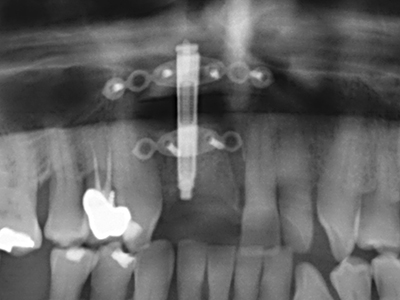

Fig. 24: applicazione del distrattore (TRACK-System, KLS Martin).

Fig. 25: panoramica dopo il raggiungimento dell'altezza finale della distrazione, prima del periodo di consolidamento.

Fig. 26: condizioni stabili prima di posizionare l'impianto, trascorso un periodo di consolidamento di quattro mesi.